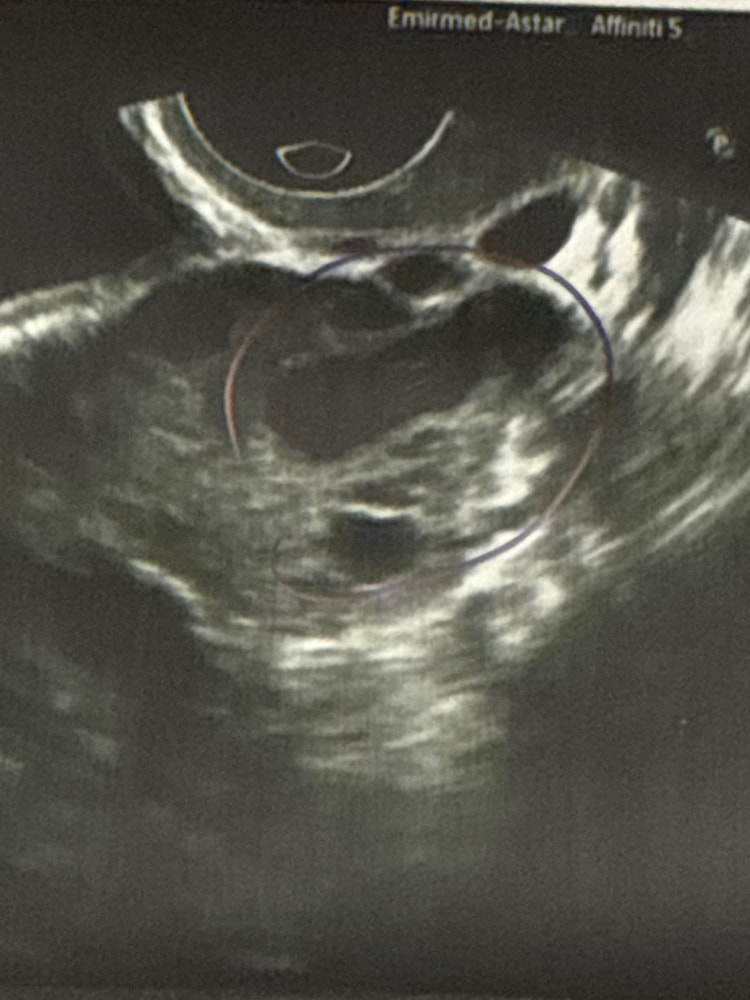

Луна, согласна :( поэтому сюда в форум прибежала. Прикрепила сегодняшнее узи Изображение

18.03.2025

Первое УЗИ - это и было ЖТ скорее всего, и оно маленькое, скорее уходит в регресс. И это не киста далеко. УЗИстам веры на 10%< вечно не видят, фантазируют, не находят, додумывают и чушь несут. Если М через 1-3 дня придут, то я права.